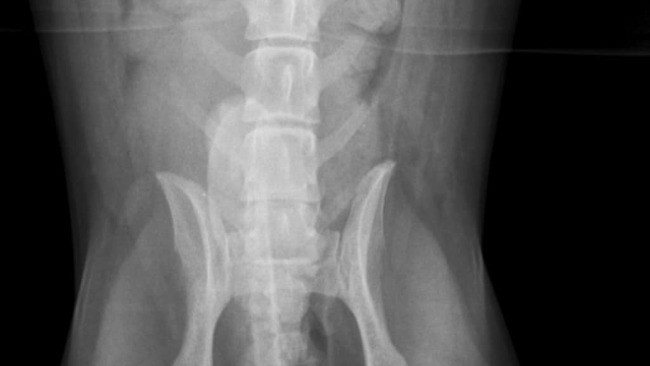

W samym środku lasu, z dala od ludzi i pomocy, znaleziono małego, biszkoptowego psiaka — wycieńczonego, zdezorientowanego, który ciągnął za sobą tylne łapy. Wszyscy, którzy go zobaczyli, byli przekonani, że to koniec… że ma przerwany rdzeń kręgowy i już nigdy nie stanie na nogi.

Na szczęście Gucio trafił na dobrych ludzi, którzy nie przeszli obok obojętnie.Został zgłoszony do pani Magdy, prowadzącej schronisko w Rytlowie, która natychmiast zorganizowała dla niego pomoc i opiekę.Po szybkiej konsultacji w przychodni weterynaryjnej Hesse we Włoszczowie, Gucio trafił do gabinetu Cztery Łapy w Kielcach, gdzie opiekę nad nim przejął dr Kabała.Tam rozpoczęła się walka o jego zdrowie i powrót do sprawności — badania, diagnostyka, operacja i rehabilitacja .